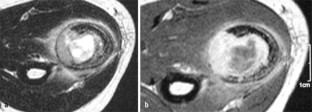

MRI morphology of bone tumors and tumor-like lesions

Für das Staging und die Charakterisierung von Knochentumoren und tumorähnlichen Läsionen ist in der Magnetresonanztomographie (MRT) der Einsatz von Spinechosequenzen erforderlich. Die MRT hat nur einen geringen Stellenwert in der Bestimmung der Dignität. Obwohl viele Knochentumoren und tumorähnliche Läsionen eine vergleichbare Morphologie in dieser bildgebenden Modalität aufweisen, können einige Tumorentitäten mittels MRT recht zuverlässig diagnostiziert werden. Hierzu zählen Knorpeltumoren, die solitäre und aneurysmatische Knochenzyste, der Riesenzelltumor, fetthaltige Läsionen und bis zu einem gewissen Grad auch das Osteoidosteom und das Osteoblastom. Es werden praktische Tipps gegeben, wann bei Tumorverdacht die MRT eingesetzt werden sollte, wie bei einem zufällig bei einer MRT gefundenen Tumor die Untersuchung modifiziert werden sollte und welcher Tumor vorliegen könnte.

Spin-echo sequences are mandatory at MRI for staging and characterization of bone tumors and tumor-like lesions. MRI is of minor value in the estimation of the malignant potential of an osseous lesion. Although many bone tumors and tumor-like lesions present similar morphology at MRI, some entities can be diagnosed with good reliability. These include chondrogenic tumors, solitary and aneurysmal bone cysts, giant cell tumors, lesions containing fatty tissue and, to a certain extent, osteoid-osteomas and osteoblastomas. Practical advice is given regarding when to perform a MRI study in cases of tumor suspicion. Further advices are given for cases a tumor is found incidentally at a MRI study, how to modify the study and which kind of tumor may be present.